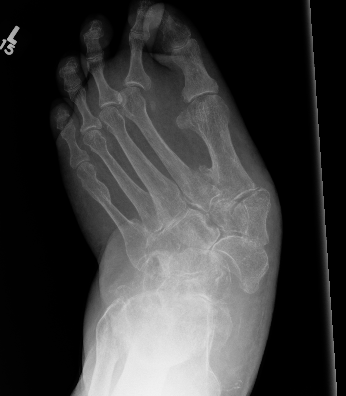

Absorption of osseous debris Organization and early healing of fracture fragments Periosteal new bone formation |

Smoothing of edges Oosseous or fibrous ankylosis Bone healing Resolution of osteopenia

Midfoot dissolution, coalescence and reconstruction

Midfoot collapse

Midfoot collapse and rocker bottom foot with small ulcer